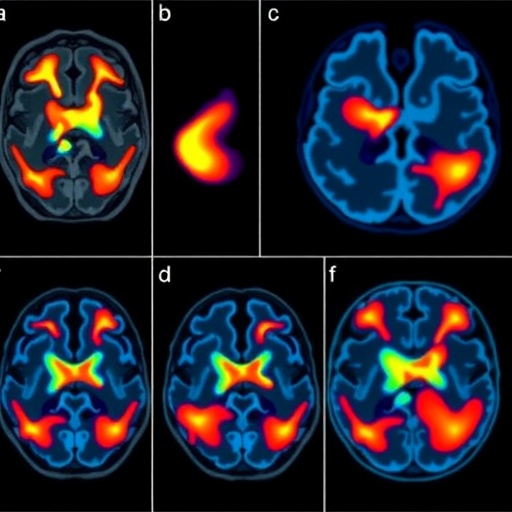

Electrophysiologically, the research unraveled that resting tremors correlate with oscillatory activity predominantly within the beta frequency range (~13-30 Hz) in the subthalamic nucleus. Contrastingly, action tremors engage broader motor circuits, implicating cortico-subcortical loops and possibly cerebellar pathways. This nuanced understanding stems from long-term neural recordings analyzed during different motor states, lending unparalleled insight into tremor dynamics over time.

The research also underscores the critical role of advanced neuroimaging and electrophysiological monitoring in PD management. By integrating these technologies, clinicians can now visualize the intricate pathways involved in different tremor phenomenologies, informing both surgical target selection and postoperative programming. The potential for closed-loop DBS systems that respond dynamically to real-time neural markers looms on the horizon, promising hefty improvements in symptom control.